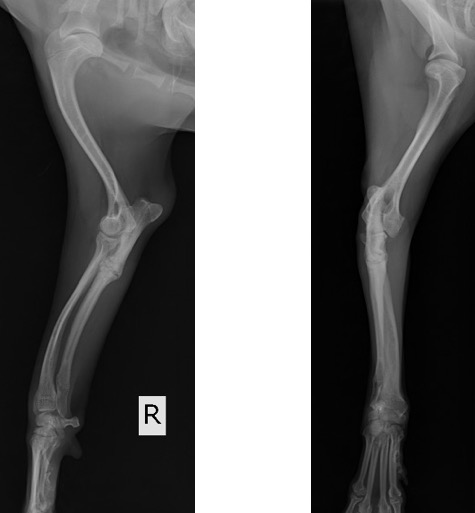

チワワ 去勢雄 8ヵ月齢

静止時、および歩行時において右前肢の挙上を主訴に来院されました。

単純X線画像検査において、右側の尺骨遠位成長板領域の不透過性亢進、橈骨の頭側湾曲、鈎状突起と上腕骨顆の間隙が広がっている所見が認められたため、尺骨遠位成長板早期閉鎖が疑われました。

前腕のLateral像 (黄丸;尺骨遠位成長板の不透過性亢進 青矢印:橈骨の湾曲 赤矢印:鈎状突起と上腕骨顆の間隙)

前腕のAP像 (黄丸:尺骨遠位成長板の不透過性亢進 青矢印:橈骨の湾曲)